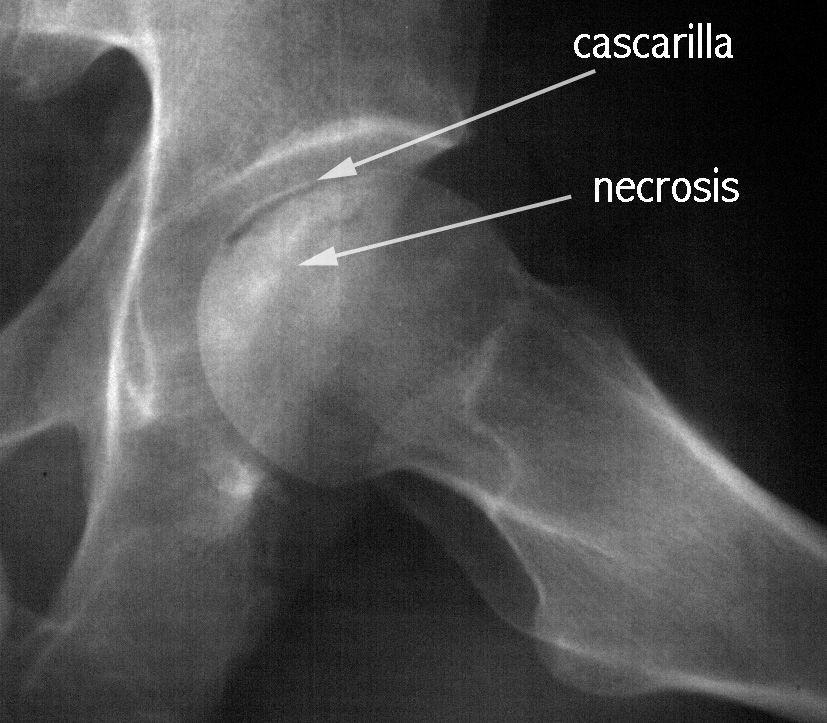

SE APRECIA UNA LINEA DE COLAPSO SUBCONDRAL EL SIGNO DE LA MEDIA LUNARADIOLOGIA NORMAL EL DIAG SE PUEDE REALIZAR POR RESONANCIA MAG

Secuencias Radiológicas

COLAPSO AFECTA LA SUPF SUBCONDRAL PERDIENDO SU MORFOLOGIA NORMAL